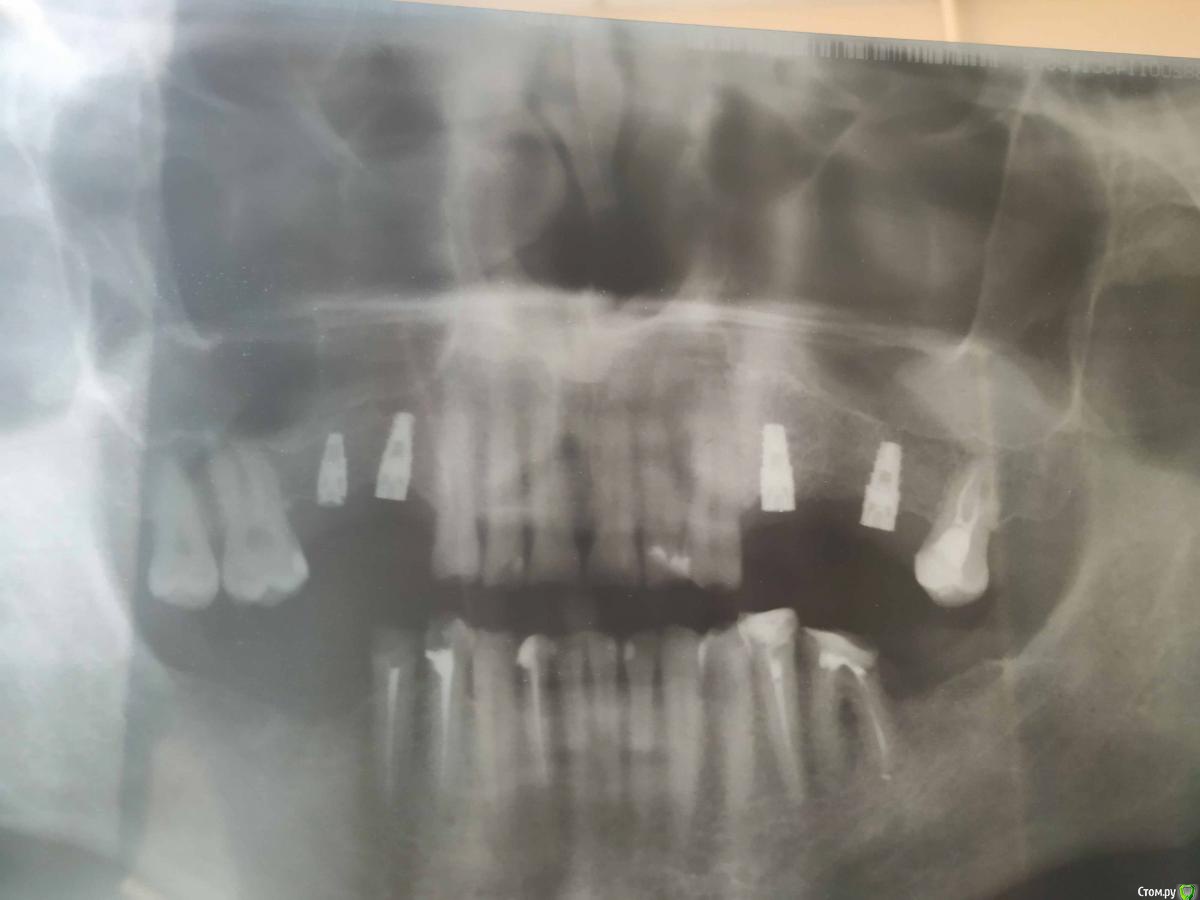

Владимир Серпухов Опубликовано 17 апреля, 2019 Поделиться Опубликовано 17 апреля, 2019 (изменено) Добрый день, хорошие моиЯ Владимир, 38 лет, проживаю в Серпухове, имплантация в Туле.Верхние зубы отсутствуют уже лет 15.Операцию начали 12.04.19 в 15.30, закончили в 16.00Затем цифровой панорам снимок - винты в кости, до гаймор пазух слава Богу не доставли.Сказали через 2 месяца приезжать.Ответьте на пару вопросов пожалуйста:1. Мне и правда не надо было синус-лифтов никаких делать?2. Слева врач предлагает имплант+имплавнт+последний зуб = один мост. На ваш взгляд верно? Я переживаю, что если свой зуб заболит, ето надо всю конструкцию имплантную снимать. Может все-таки свой зуб к имплантам не не надо? Изменено 17 апреля, 2019 пользователем Владимир Серпухов Ссылка на комментарий

Владимир Серпухов Опубликовано 18 апреля, 2019 Автор Поделиться Опубликовано 18 апреля, 2019 Чет ночью сегодня на 6ой день левый винт тот что ближе к клыку болел((Посмотрите пожалуйста, что нить на снимке видно нехорошего? Ссылка на комментарий